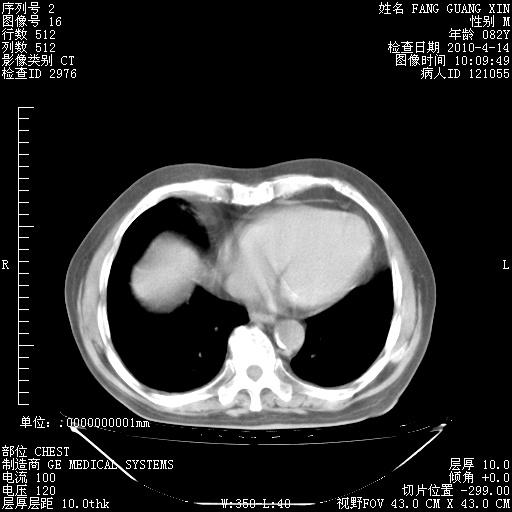

4月14日肺部CT